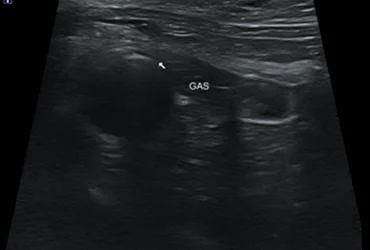

1. 복부 초음파 검사

간, 담낭, 췌장, 위장관 등의 구조적 이상을 평가하여 질환의 유무를 확인합니다. 실시간 영상으로 장기의 형태, 크기, 내부 구조를 정밀하게 모니터링합니다.

비침습적이고 안전하게 소화기계 문제를 스크리닝하고 진단합니다.